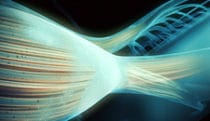

Blood flow dynamics of the heart